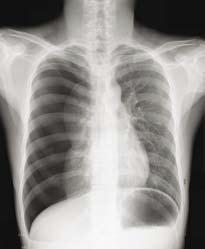

■從X光照片中,可以見到患者的左肺因氣胸而被空氣壓至萎縮。